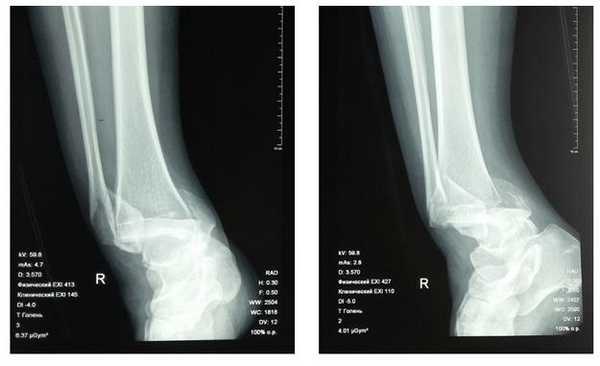

Пациент П., 45 лет, получил травму пяточных костей при падении с высоты 2 м. Избранный метод лечения - консервативное - был безуспешным. При поступлении в институт установлен диагноз: внутрисуставной импрессионный перелом пяточной кости (рис.1 а, б, в. - рентгенограммы в разных проекциях). Через 2 недели после травмы проведена операция по предлагаемому способу. Сначала был наложен дистракционный аппарат (рис. 2) и осуществлена дистракция под контролем электронно-оптического преобразователя. Далее производится проведение спицы по оси пяточной кости (рис. 3). По проведенной спице канюлированным сверлом осуществляют формирование канала до импрессированного отломка пяточной кости (рис. 4).

Проведение репозиции суставной поверхности пяточной кости осуществляется применением элеватора, введенного в кость через сформированный канал (рис. 5). При достижении удовлетворительного стояния отломков их компрессия осуществляется введением спонгиозных винтов диаметром 3,5 мм через проколы кожи, без осуществления больших операционных доступов.